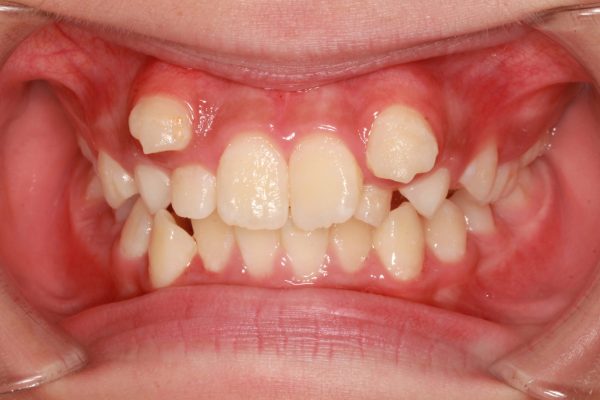

21歳の 女性です。

「 八重歯を 治してほしい 」との事で来院されました。

典型的な ”八重歯” の状態です。

犬歯(中心から3番目の歯)が外に飛び出しています。

この犬歯の影響で口内炎が絶えないのが悩みとの事です

これだけ出ていると唇が常に擦れますよね・・・ お辛いと思います

前歯 4本のうち、2本が 逆に噛んでいます

上の八重歯に目が行きがちですが、下の歯ならびも、乱れた状態ですね